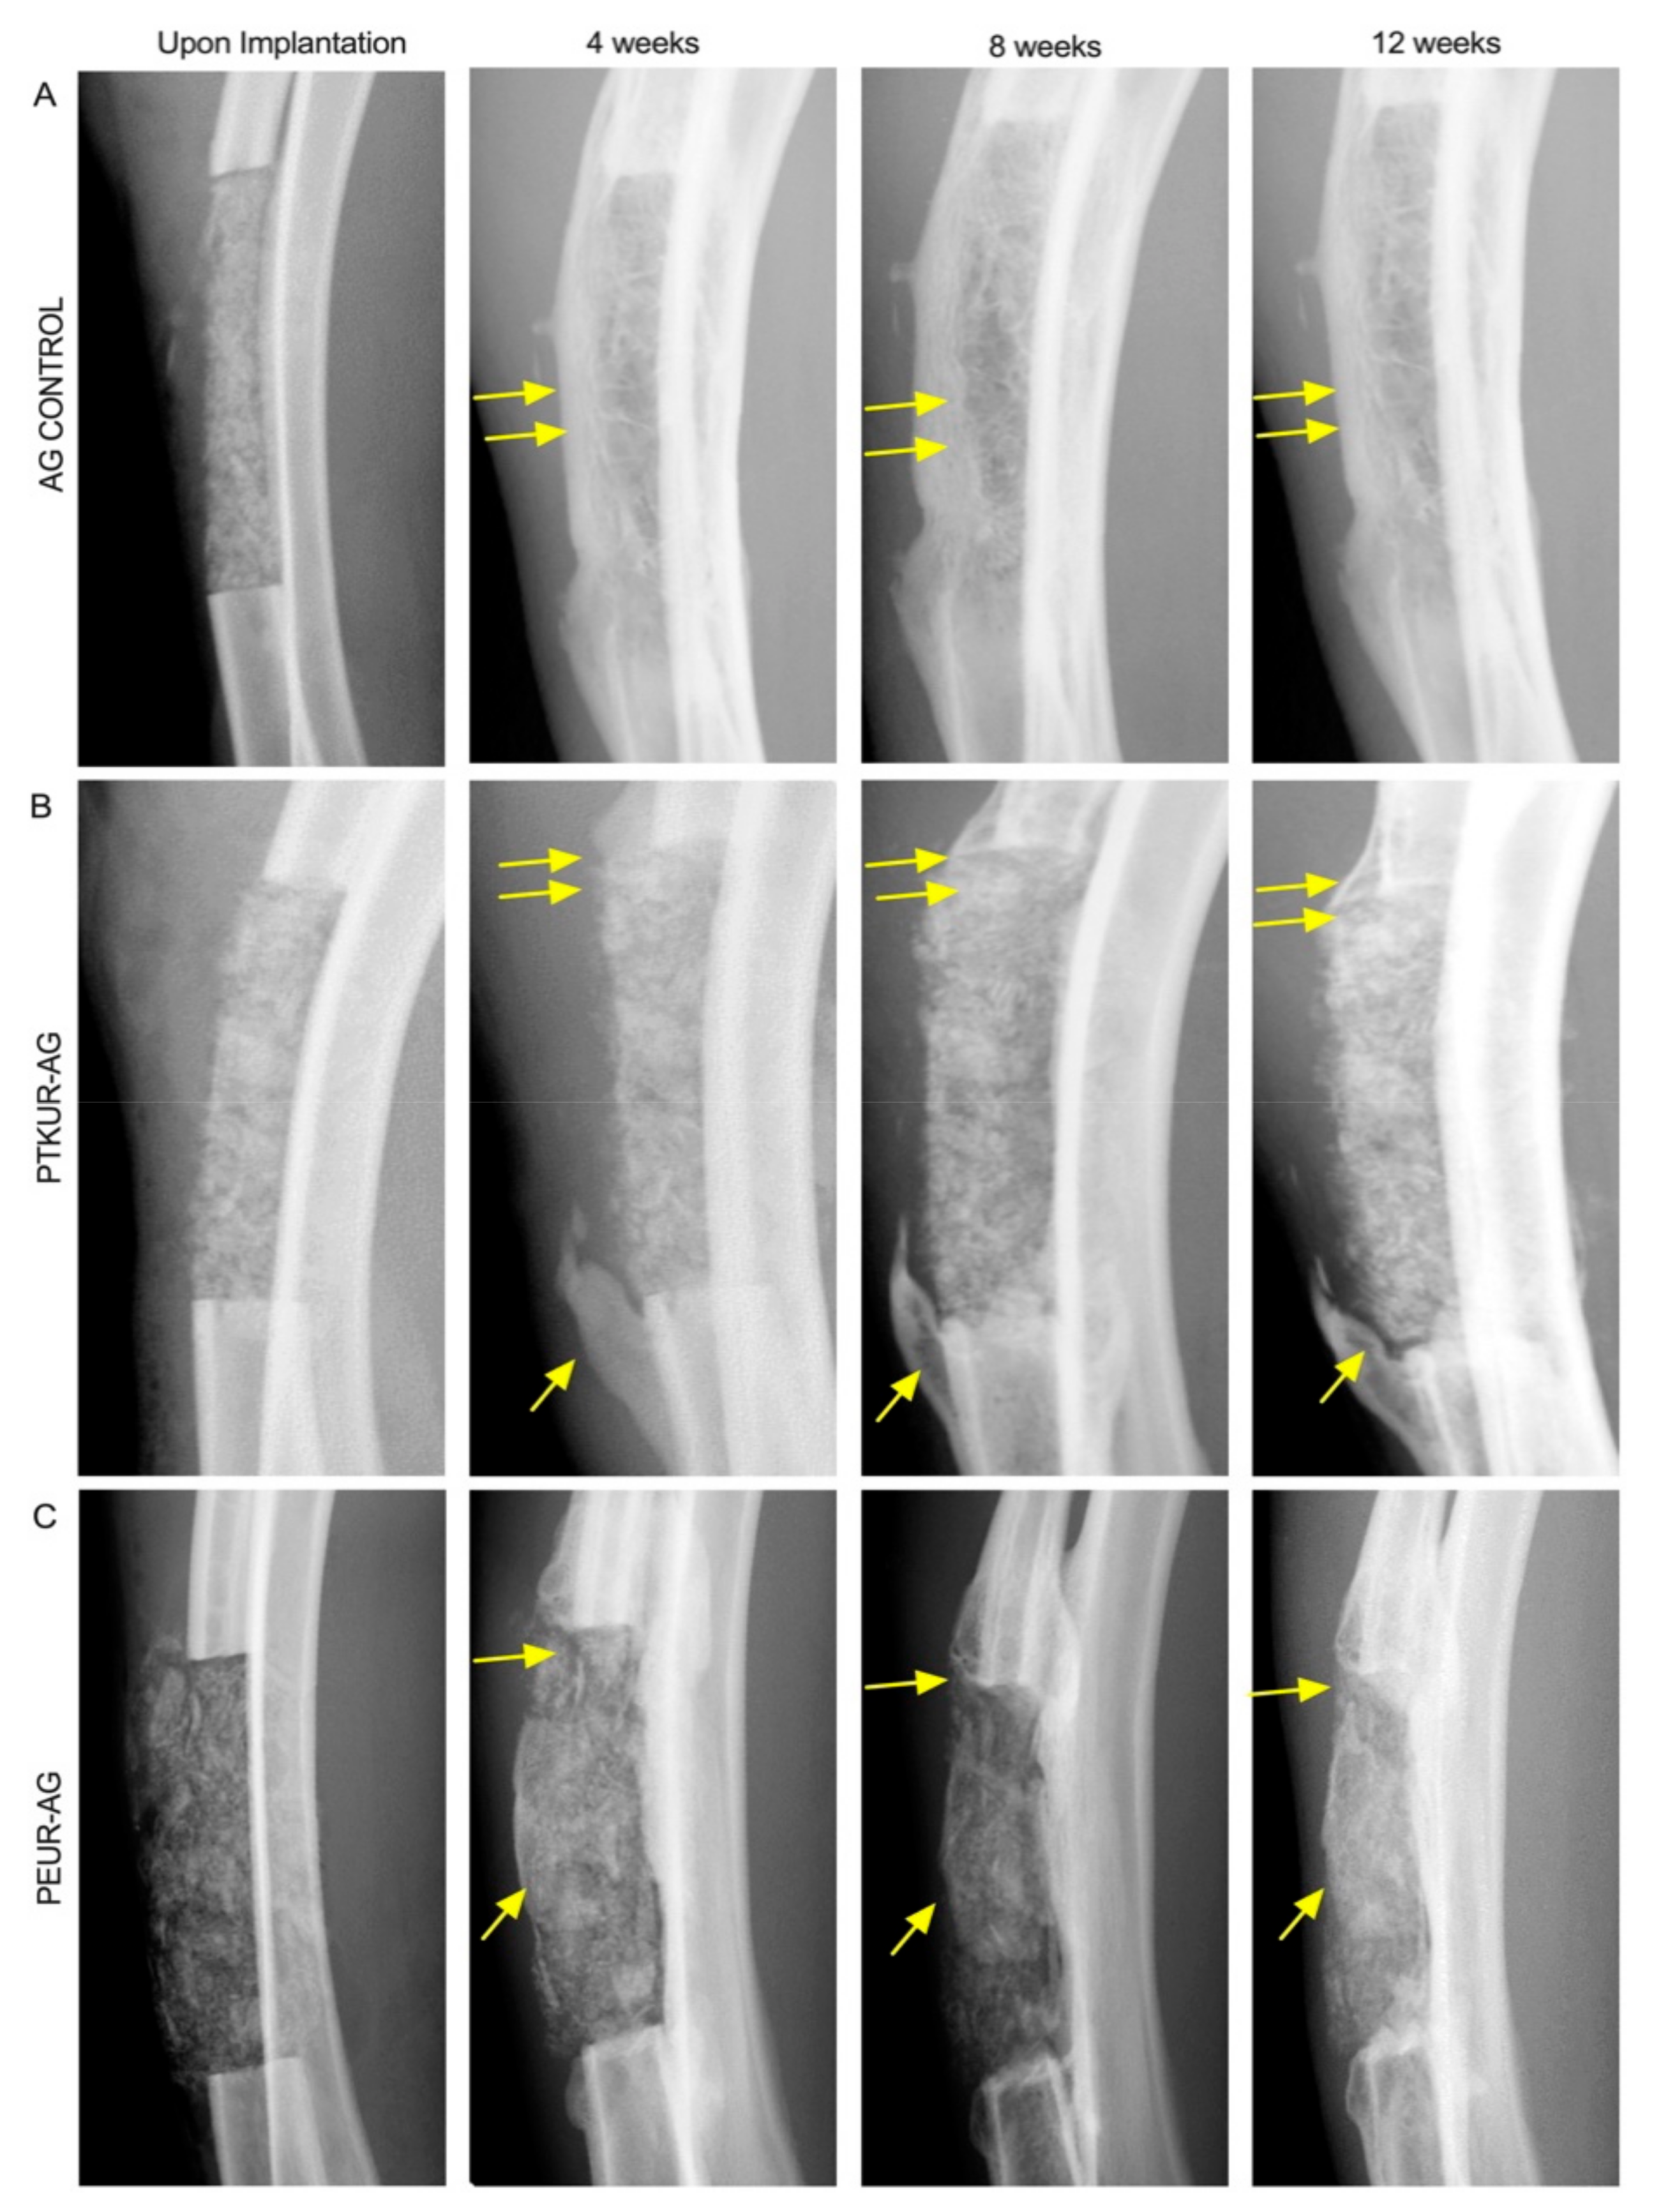

3.2. In Vivo Bone Analysis

3.3. PTKUR and PEUR Graft Remodeling